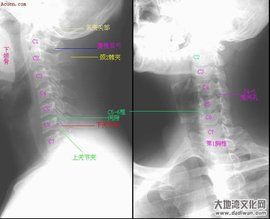

症狀以發作性眩暈為主,眩暈發作與頸部鏇轉或後伸運動或體位急劇變動有關,以伴有復視及無意識障礙的猝倒為特徵。X線片表現為上頸段或下頸段有節段性不穩或鉤椎關節骨贅橫向增生,無神經系統陽性體徵。

椎動脈系列圖(2)椎動

椎動脈圖1椎動脈型頸椎病的病因,椎動脈型頸椎病是由於頸椎不穩、退變,骨刺直接刺激、壓迫椎動脈,或者由於刺激了頸椎關節囊韌帶和椎動脈壁周圍的交感神經引起的反射性椎動脈痙攣而導致椎動脈供血不足的一種疾病。 椎動脈型頸椎病的病因列舉。